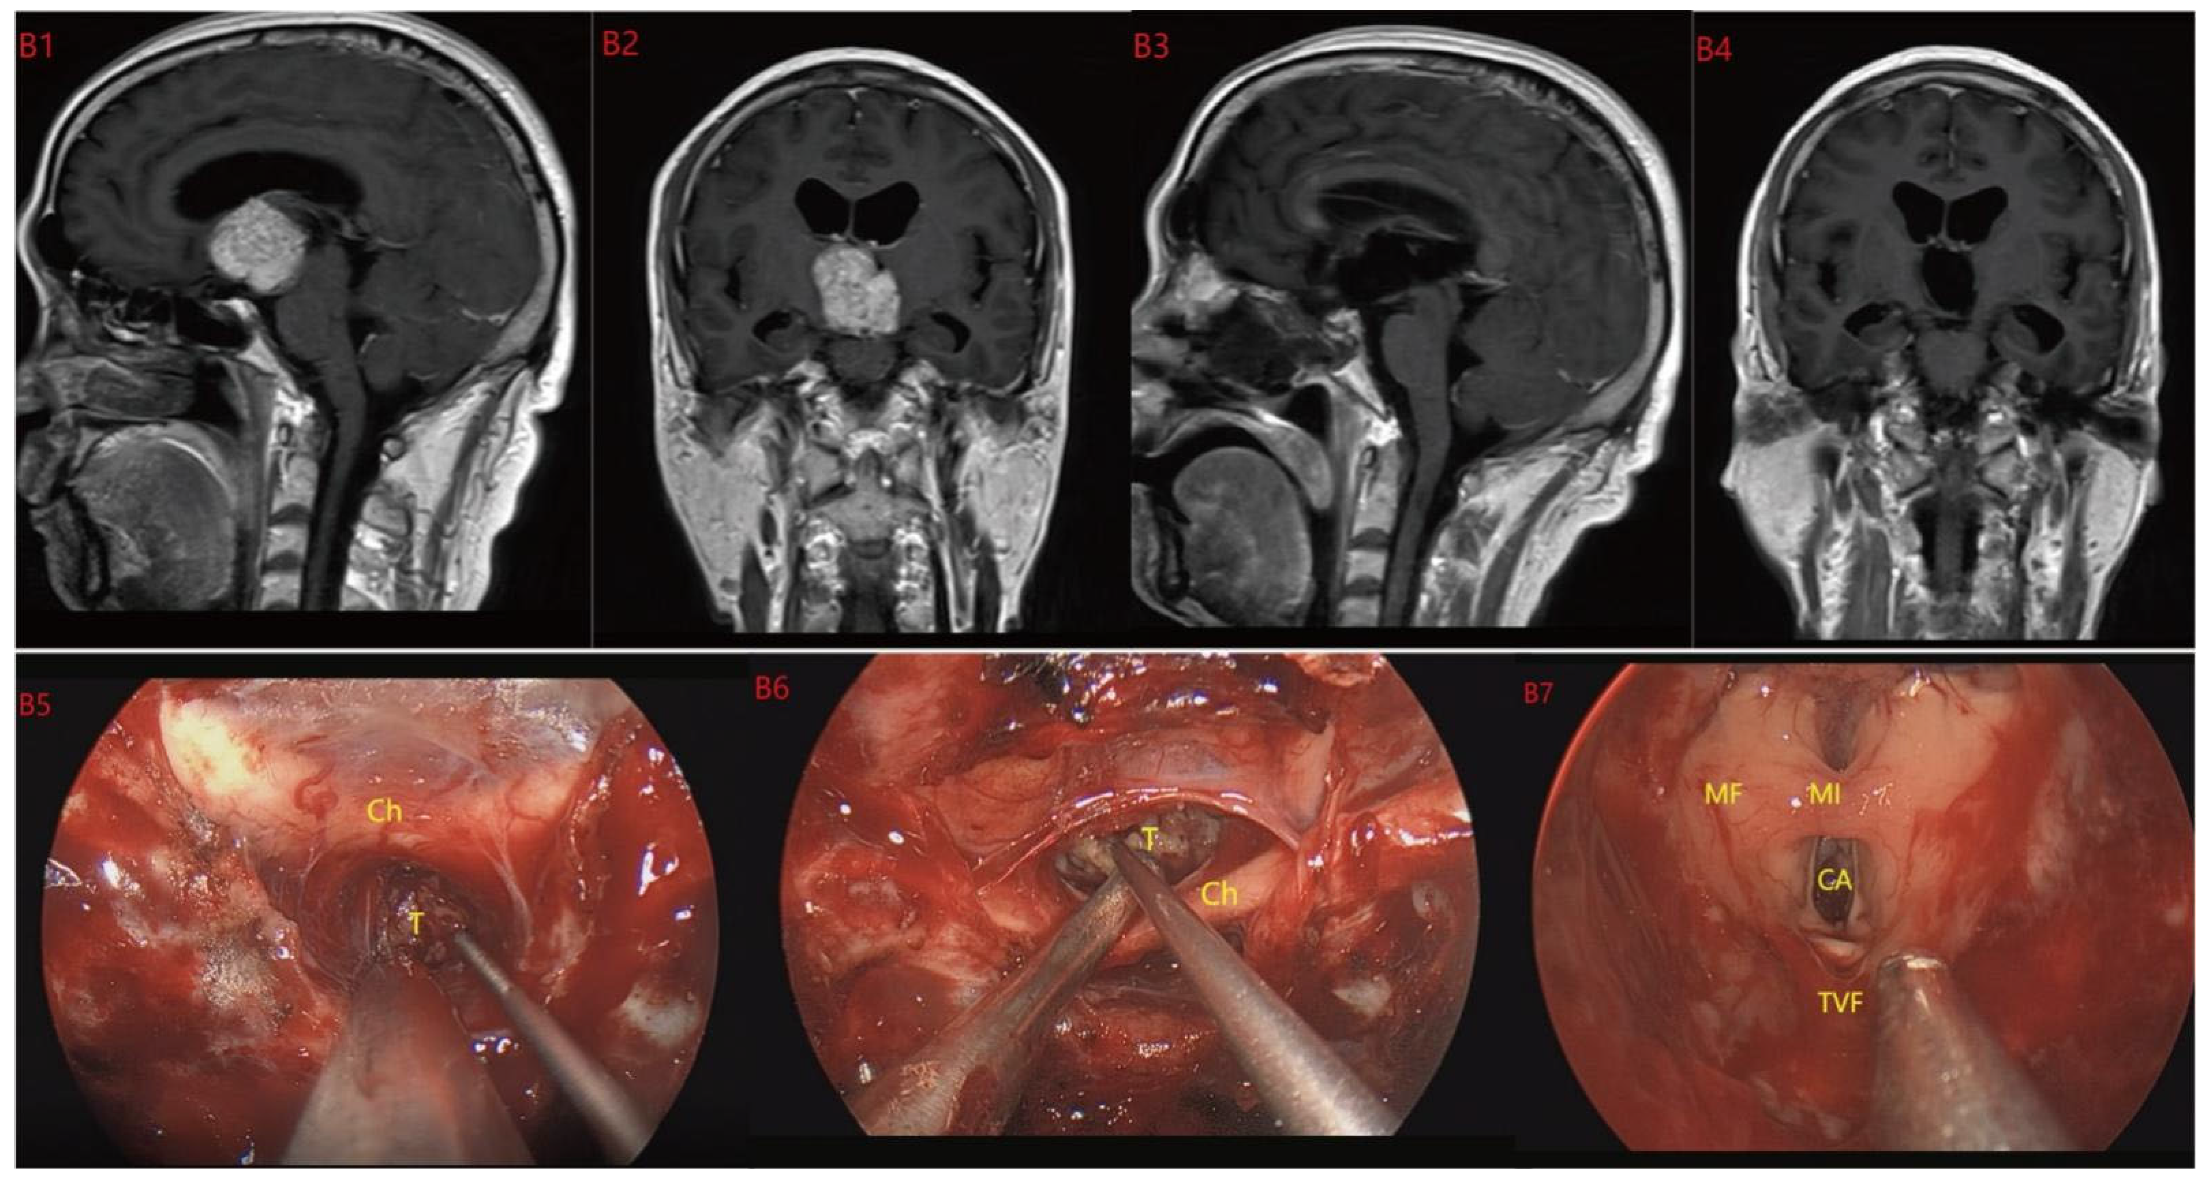

Figure 3.

Case 3 Type II: (B1,B2) The tumor was located on the suprasellar, growing upwards into the third ventricle, and it is impossible to judge whether the third ventricle floor was complete before operation. During the EEA surgery (B5–B8), the TCPCA and TLTA was used. The tumor was completely resected (B3,B4), and the floor of the third ventricle was seen to be incomplete. Optic chiasm (Ch), foramen of Monroe, massa intermedia (MI), cerebral aqueduct (CA), tumor (T).